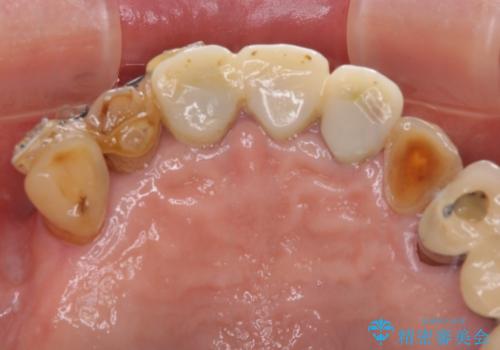

- 前歯の部分矯正や仮歯に置き換えるなど、治療途中のまま放置してしまったとのことで来院された患者様です。

骨格的に下顎骨が前方にあり、歯列の幅も下顎の方が大きいため、奥歯に負担のかかりやすい咬合でした。

大臼歯部は、上下左右ともに咬合により問題が生じており、骨格的な問題から積極的な治療をするべきか判断の難しい状況でした。

臼歯部は痛みが生じている歯に絞って処置を行い、それ以外については手を加えず、現状維持を心がけることとしました。

前歯部については抜歯が必要な歯を抜歯し、インプラントやブリッジなどにより補綴治療を行うこととしました。